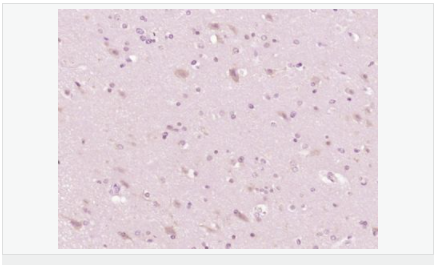

| 產(chǎn)品應用 | WB=1:500-2000 ELISA=1:5000-10000 IHC-P=1:100-500 IHC-F=1:100-500 ICC=1:100 IF=1:100-500 (石蠟切片需做抗原修復) not yet tested in other applications. optimal dilutions/concentrations should be determined by the end user. |